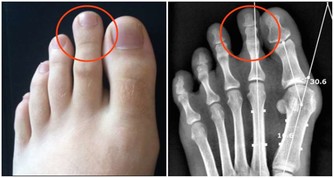

小小感染,也易引發糖尿病足

在我國,大約85%的下肢截肢是糖尿病足引起的。

糖尿病引起的下肢血管病變和合併感染,是引起糖尿病足最主要的原因。

一方面,糖尿病性下肢血管病變,會導致足部局部缺血缺氧,延遲傷口癒合;

另一方面,高血糖使患者自身免疫功能下降,對感染的防禦能力降低,有利於細菌的繁殖。

因此,各位糖友需要注意,保護自己的雙足,避免受傷和乾擾,從而引發糖尿病足。